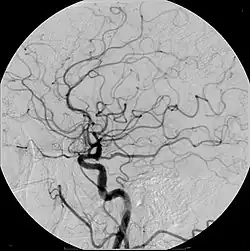

Angiografie bzw. Angiographie (Wortteil Angio- von griechisch ἀγγεῖον ‚Gefäß‘) nennt man in der Medizin die ab 1923/1924 eingeführte radiologische Darstellung von Gefäßen, meist Blutgefäßen mittels diagnostischer Bildgebungsverfahren, beispielsweise Röntgen oder Magnetresonanztomografie (MRT). Hierzu wird häufig ein Kontrastmittel in das Blutgefäß injiziert. Auf dem Bild der aufgenommenen Körperregion zeichnet sich dann der mit dem Kontrastmittel gefüllte Gefäßinnenraum ab. Das resultierende Bild nennt man Angiogramm. Mit der MRT sind auch Angiografien ohne Kontrastmittel möglich, wodurch man sich die invasive Punktion des Gefäßes erspart.

- Die zerebrale Angiografie wurde 1927 von dem portugiesischen Arzt und Politiker António Egas Moniz und dessen Mitarbeiter Pedro Manuel de Almeida Lima als Röntgenkontrastdarstellung des intrakraniellen Gefäßsystems von der Arteria carotis aus entwickelt. Ab 1931 erprobte er auch den Zugang über die Axillararterie und verwendete er als Kontrastmittel das später wieder verlassene radioaktive und giftige Thoriumdioxid.[1] Später wurden andere Kontrastmittel eingesetzt.[2] Die zerebrale Angiografie erfuhr durch die Einführung des Seldinger-Katheters zu Beginn der 1950er Jahre eine Erleichterung ihrer Anwendung.[3]

Zunächst wird ein Katheter oder eine Injektionsnadel in das Gefäßsystem eingebracht und dann im bzw. vor den Abgang des interessierenden Blutgefäßes positioniert. Vor Gabe des Kontrastmittels kann ein normales Bild (Leeraufnahme) von der untersuchten Körperregion angefertigt werden. Wird dann das Kontrastmittel über Katheter bzw. Nadel in das Gefäß gespritzt, werden davon in schneller Abfolge Aufnahmen angefertigt. Sollten diese Bilder in digitaler Form gespeichert werden, kann man von den Angiografiebildern die Leeraufnahme subtrahieren. Störende Bildelemente, die auf beiden Bildern vorhanden sind (z. B. Knochen), werden dadurch ausgeblendet, was die Auswertung der Aufnahmen erleichtert (digitale Subtraktionsangiografie).

Die Angiografie zeigt die Kontrastierung der untersuchten Gefäße mit dem Blutfluss und bietet damit die Kombination aus morphologischer Information über das Füllungsbild und funktioneller Information über An- und Abflussverhalten des Kontrastes als Ausdruck der Hämodynamik. Größter und einzigartiger Vorteil der Angiografie ist, dass während der Untersuchung auch Eingriffe im Gefäß vorgenommen werden können. Verengte Gefäße können aufgedehnt (Angioplastie), Blutgerinnsel aufgelöst und Aneurysmata ausgeschaltet werden. Auch können verschobene Katheter unter Umständen wieder korrekt ausgerichtet werden.